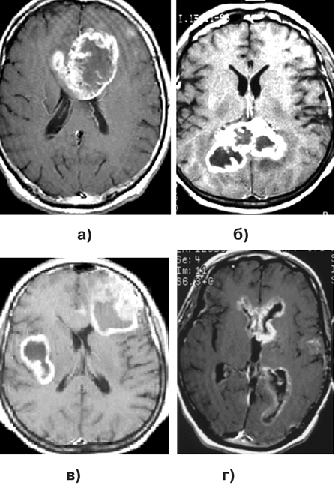

На КТ плотность опухоли весьма гетерогенна (рис. 4а). Центральная зона низкой плотности представляет некроз, выявляемый в 95% случаев. Границы опухоли нечеткие. Петрификаты встречаются редко. Часто определяются кровоизлияния различной давности. Опухоль обычно окружена зоной перифокального отека, распространяющегося в белом веществе больших полушарий. ГБ обычно активно накапливают контраст. Усиление после введения контрастного вещества выражено часто неоднородно, контрастирование имеет характерный вид кольца с неоднородным внутренним контуром. В ряде случаев ГБ отсутствует узловой компонент, и опухоль растет инфильтративно, широко поражая полушарие. Рентгенологически признаки повреждения ГЭБ (накопление контраста) при этом нередко отсутствуют, и контрастное усиление мало изменяет характеристику сигнала от опухоли.

МР-проявления ГБ в целом отражают патоморфологические изменения, демонстрируя значительную гетерогенность опухоли. На Т1-взвешенных томограммах выявляется плохо отграниченное объемное образование со смешанным (изогипоинтенсивным) сигналом, центральным некрозом, которому соответствует сниженный по отношению к опухолевой массе сигнал (рис. 3в, 4в). На Т2-взвешенных изображениях выявляются участки гипо-, изо-, гиперинтенсивного сигнала от стромы ГБ, зоны некроза, кист и кровоизлияний. Выраженный “масс-эффект” и распространенный отек белого вещества часто сопровождают и небольшие по размерам опухоли (рис. 4б). Границы опухоли сливаются с перифокальным отеком.

Рисунок 4. Глиобластома правой височно-теменной области, распространяющаяся на подкорковые узлы:

а — КТ с контрастным усилением; б — МРТ, Т2-взвешенные изображения; в — МРТ, Т1-взвешенные изображения, с контрастным усилением; г — каротидная АГ

Как и при АА, опухолевые клетки ГБ могут быть обнаружены за пределами зоны усиления сигнала и перифокального отека, выявляемых при МРТ. ГБ широко и быстро распространяются по трактам белого вещества. Типично также распространение на противоположное полушарие через мозолистое тело, переднюю и заднюю комиссуры, реже вдоль внутренней и наружной капсул (рис. 5а, б, г). При полушарных ГБ иногда определяется распространение опухоли в ножки мозга и в заднюю черепную ямку.

Так как ГБ часто бывают сильно васкуляризованы (рис. 4г), то на МР-томограммах, особенно Т2-взвешенных, могут выявляться сосуды опухоли (рис. 4б). В 5% наблюдений встречаются множественные ГБ (рис. 5в), для дифференциального диагноза с метастазами необходима стереотаксическая биопсия.